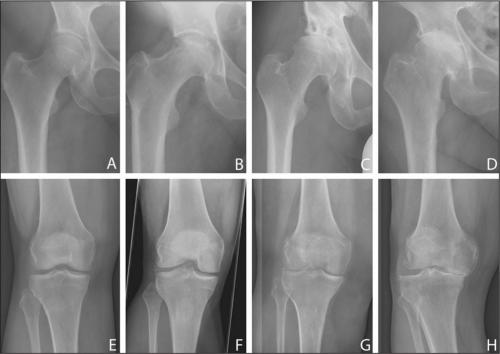

Стадии артроза коленного сустава. Обратите внимание на сужение суставной щели.

Все медикаментозные средства эффективны лишь—, но бессильныи IV. Если в патологию вовлечены не только суставы, но и кости, никакой препарат не поможет. В этом случае избавиться от хронических, трудностей при ходьбе, ограниченной подвижности суставов и других неприятных симптомов можно только с помощью операции.

Хрящ колена у некоторых людей начинает разрушаться еще до наступления 30 лет, и происходит это по разным объективным причинам. К 45 годам уже наступает полноценно развивающийся процесс разрушения хрящевой ткани, выражающийся в ее изначальном повреждении и возникновении микротрещин, затем в появлении обширного воспалительного процесса, за которым следует разрастание и деформация костной ткани. Заболевание, у которого есть общий собирательный термин артрит, развивается по нескольким причинам.

При лечении артроза колена следует подобрать правильный комплекс мер для излечения болезни. В первую очередь следует установить правильный диагноз. Чем раньше будет начато лечение, тем больше шансов на быстрое выздоровление. Обезболивающие средства следует принимать только по назначению врача. При нарушении хрящевой ткани коленного сустава принимают хондопротекторы, благодаря которым идет быстрое восстановление поврежденных хрящевых тканей. Дополнительно принимают согревающие мази, противовоспалительные кремы и сосудорасширяющие препараты. Лечащий врач может назначить накладывание различных компрессов на болезненный сустав, а также инъекции и физиопроцедуры.